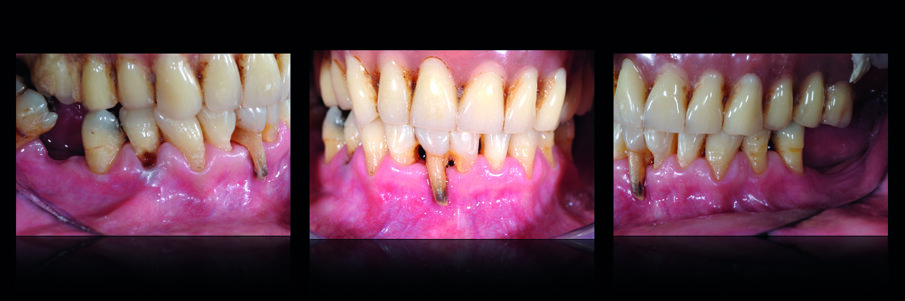

L’esame radiografico mostrava la persistenza di due impianti nel mascellare superiore (Fig. 1) uno dei quali pescava nella cavità nasale. Si osservava inoltre una lesione cistica in regione 4.1-4.2. Il trattamento dell’edentulia totale non può prescindere da una accurata analisi estetica che si concretizzerà in un’analisi Facciale, Dento-Labiale, Fonetica e Dentale. La paziente non mostrava esposizione dentale a riposo e presentava una linea del sorriso inversa (concava e non parallela al labbro inferiore) (Fig. 2). L’analisi del profilo della paziente confermava la necessità di fornire un adeguato supporto dei tessuti peri-orali nel mascellare superiore (Fig. 3). L’esame intra-orale permetteva di apprezzare l’insufficienza dell’estensione della protesi superiore, e la compromissione degli elementi dell’arcata inferiore. All’esame clinico i due impianti mostravano perdita dell’integrazione. (Figg. 4, 5).

Dopo la loro rimozione e aspettato il periodo di guarigione, sono state rilevate le impronte iniziali e, dopo aver costruito un porta-impronte ed il suo successivo bordaggio funzionale, è stata rilevata l’impronta di precisione del mascellare superiore. Sul modello master, è stato realizzato un vallo in cera che ha permesso la registrazione dei rapporti inter-mascellari e il montaggio dei modelli in articolatore tramite arco facciale. Sono state così realizzate una protesi rimovibile provvisoria superiore e una protesi fissa inferiore. In una seduta successiva sono stati estratti gli elementi inferiori non recuperabili e la protesi fissa inferiore è stata ribasata e stabilizzata sui pilastri residui (Fig. 6). Sono stati successivamente valutati i parametri funzionali ed estetici comparandoli con la situazione iniziale (Fig. 7), osservando il miglioramento della qualità del supporto dei tessuti periorali (Fig. 8). La fase successiva ha previsto la terapia implantare: previa adeguata ceratura è stata realizzata una guida chirurgica che ha permesso il posizionamento ideale degli impianti dentali nell’arcata inferiore (Fig. 9).